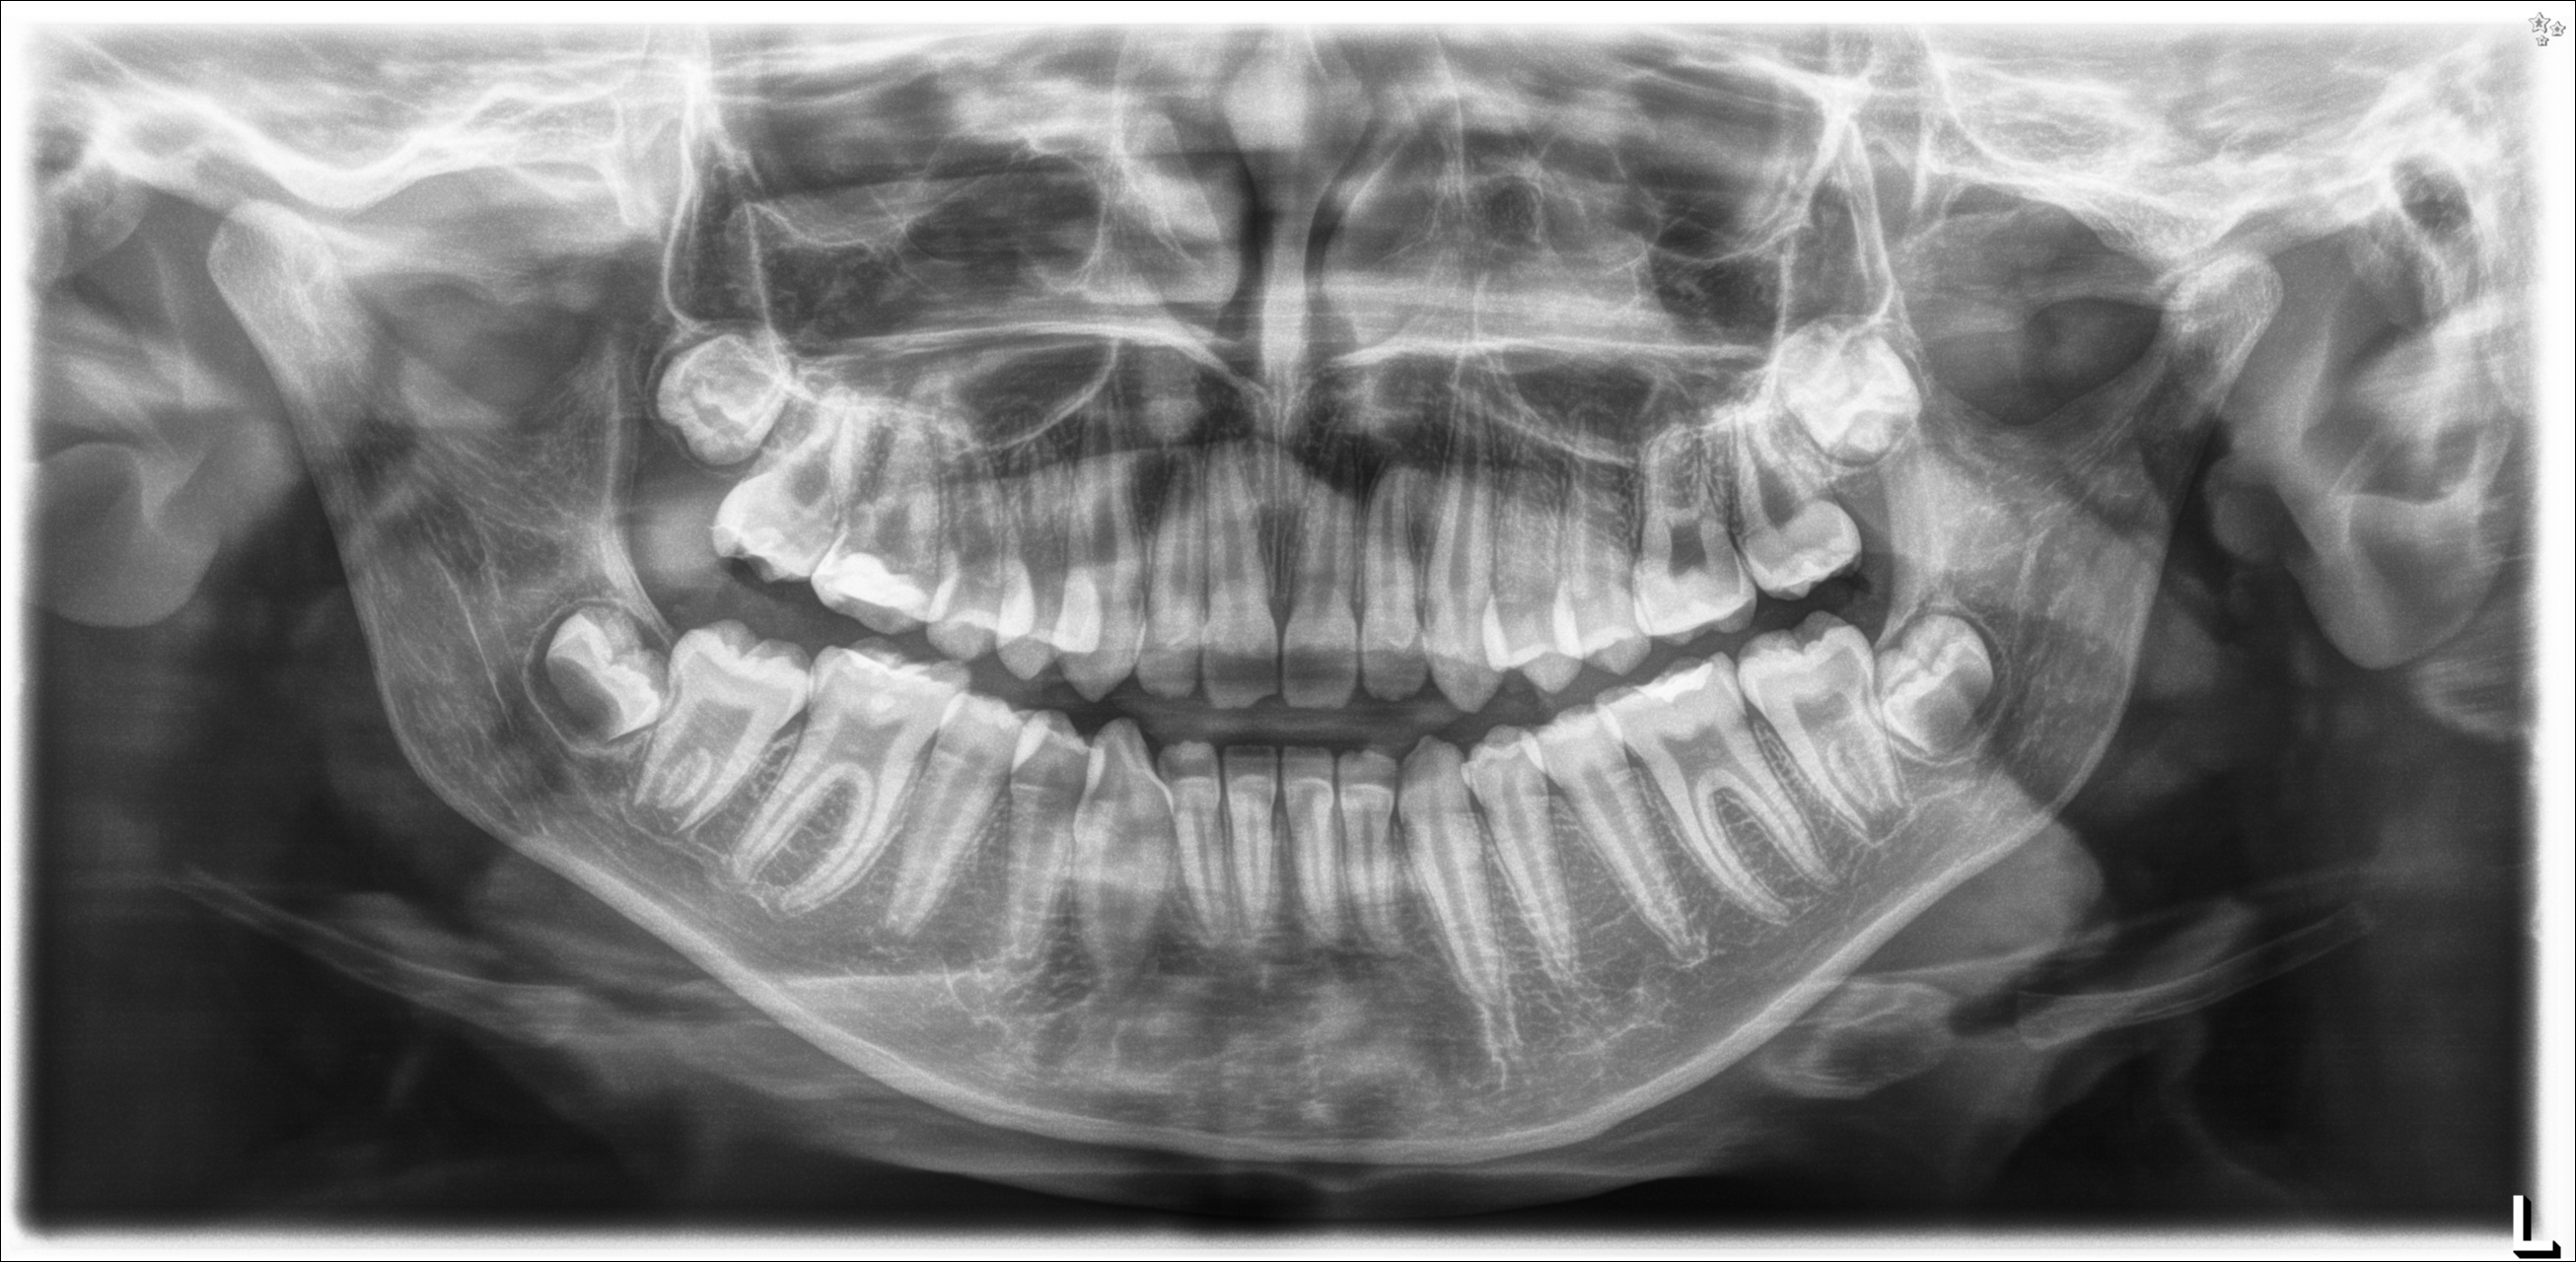

ORTOPANTOMOGRAFIA

Sono presenti tutti i denti, compresi i germi dei denti del giudizio.

OTP

L'Otp è la radiografia della bocca del paziente. L'immagine qui sotto descrive la complessità del trattamento.